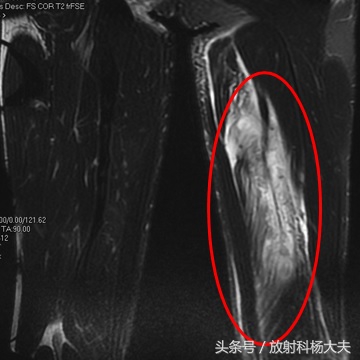

肌肉拉伤可能是足球场上最多见的损伤了,为啥有的拉伤冷敷,休息就能好,而有的拉伤得做手术,甚至有可能导致职业生涯终止?其实答案都在MRI上,用MRI看肌肉有无拉伤,拉伤的程度如何,是目前最好的选择。

在MRI上,少于5%肌肉纤维的断裂,为I级损伤,大于5%,但没完全断裂的为II级损伤;完全断裂则为III级。比较多见的是I级损伤,MRI上可以看到肌肉的轮廓存在,但能看到白白的一片,代表水肿。